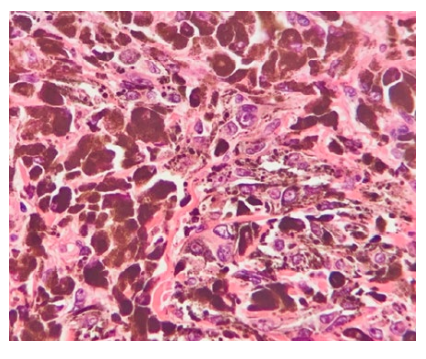

The lesion was promptly excised. Histopathology showed a circumscribed, symmetrical, wedge-shaped dermal proliferation composed predominantly of pigmented epithelioid cells and dendritic cells. The cells had large nuclei and prominent nucleoli. In some areas multinucleated cells were found. No mitotic figures were identified.

Figure 3: Pigmented epithelioid and dendritic cells with large nuclei and prominent nucleoli (H&E x400).